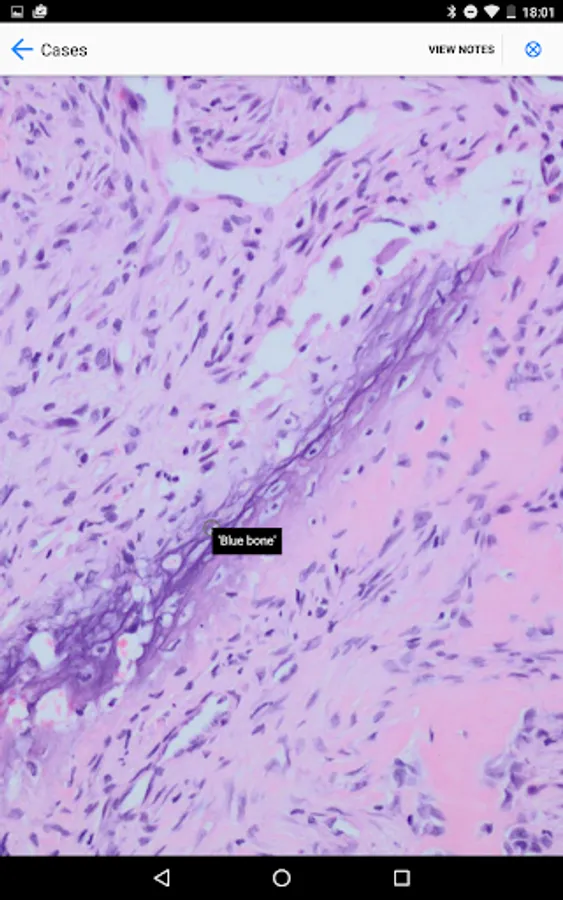

BoSTT brings the user a real experience of frequent and rare, typical and more unusual cases of bone and soft tissue tumours. Each case has a clinical history, high resolution radiology and pathology images, diagnosis, treatment and learning points.